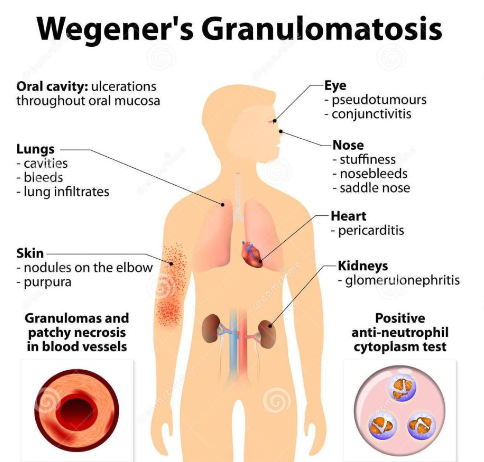

What is another name for granulomatosis with polyangiitis?

Wegener Granulomatosis

What is the cause of granulomatosis with polyangiitis?

Abnormal immune reaction, it causes vasculitis in small and medium blood vessels

What demographic does granulomatosis with polyangiitis show up in?

M = F, average age is 40

What are the clinical features of granulomatosis with polyangiitis?

Commonly affects the respiratory system (nose, sinuses, throat, lungs)

Nose bleeds, saddle nose deformity

Kidney (most common cause of death)

What are general signs and symptoms of granulomatosis with polyangiitis?

Fever, night sweats

Fatigue, lethargy

Loss of appetite

Weight loss

What are the intraoral manifestations of granulomatosis with polyangiitis?

(2%) Strawberry gingiva is red, friable, granular gingiva, non-

specific ulcer